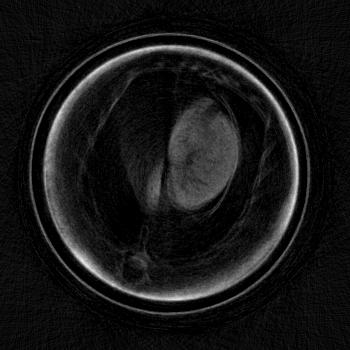

To evaluate the location of the lung tissue in the two mice computed tomographies (CT) of them were performed. This was done by rotating the object and acquiring 601 angular projections equally spaced over a full circle with the setup described in Section II.3. A reference image was taken after every 15th projection. This leads to a total of to acquire all projection images. For image reconstruction, a filtered backprojection (FBP) was applied using a ramp kernel for the absorption and the dark field data and a Hilbert kernel for the phase data after performing the phase retrieval described in Section II.2.

Exemplary for the data, one set of axial cross-sections of the lung region of the second mouse are displayed in Figure 5 (marked as horizontal lines in Figure 4). In all three CT cross-sections, the lung tissue can clearly be located in the chest of the mouse. The location found with the CT reconstruction corresponds with the location visible in the dark field projection image and the speckled area in the differential-phase image. In contrast, the exact position of the lung cannot be located with the absorption image alone.

To quantify the location of lung tissue within the mouse, a CT scan of the second mouse was performed. Its results, shown in Figure 5, substantiate the above results that lung tissue is, indeed, only present in the right part of the mouse’s chest cavity in this cross-section plane. It is imaginable that an assured diagnosis can be made without a computed tomography scan, which could lead to a quickened diagnosis and a dose saving.